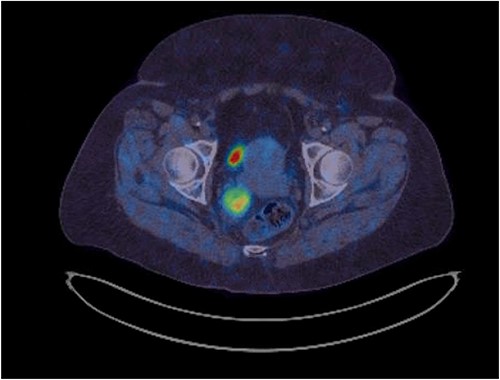

Her physical exam was normal. A right extraluminal mass was barely palpable on digital rectal examination. The pararectal mass showed no hypermetabolic activity on recent positron emission tomography (PET) scan. Either a GIST or a NET was suspected. Gallium-68 Dotatate PET scan revealed high expression of somatostatin receptors (Fig. 2). Pelvic magnetic resonance imaging (MRI) showed an isodense lesion, slightly heterogenous, on T1-weighted images with persistent T2 hyperintensity and restricted diffusion (Fig. 3). It was infiltrating the right lateral mesorectum without direct contact with the rectal wall. Colonoscopy showed no endoluminal lesion. Two ultrasound-guided fine needle aspirations (EUS-FNA) were unconclusive and patient developed osteodiscitis. Transgluteal CT-guided biopsy finally revealed the presence of thyroid tissue. Listed diagnoses were teratoma, tailgut cyst, or less likely, thyroid carcinoma. Subsequent thyroid ultrasonography revealed four non-specific micronodules. Thyroid function tests were normal, except for primary hyperparathyroidism. Parathyroid sestamibi scan suggested a single adenoma. A multidisciplinary team was made up of colorectal, head and neck, and orthopedic surgeons, along with an endocrinologist. The case was discussed at the Colorectal Tumor Board. A collaborative two-step surgical approach was proposed.

Latest pelvic MRI on initial consultation (T2-weighted images).